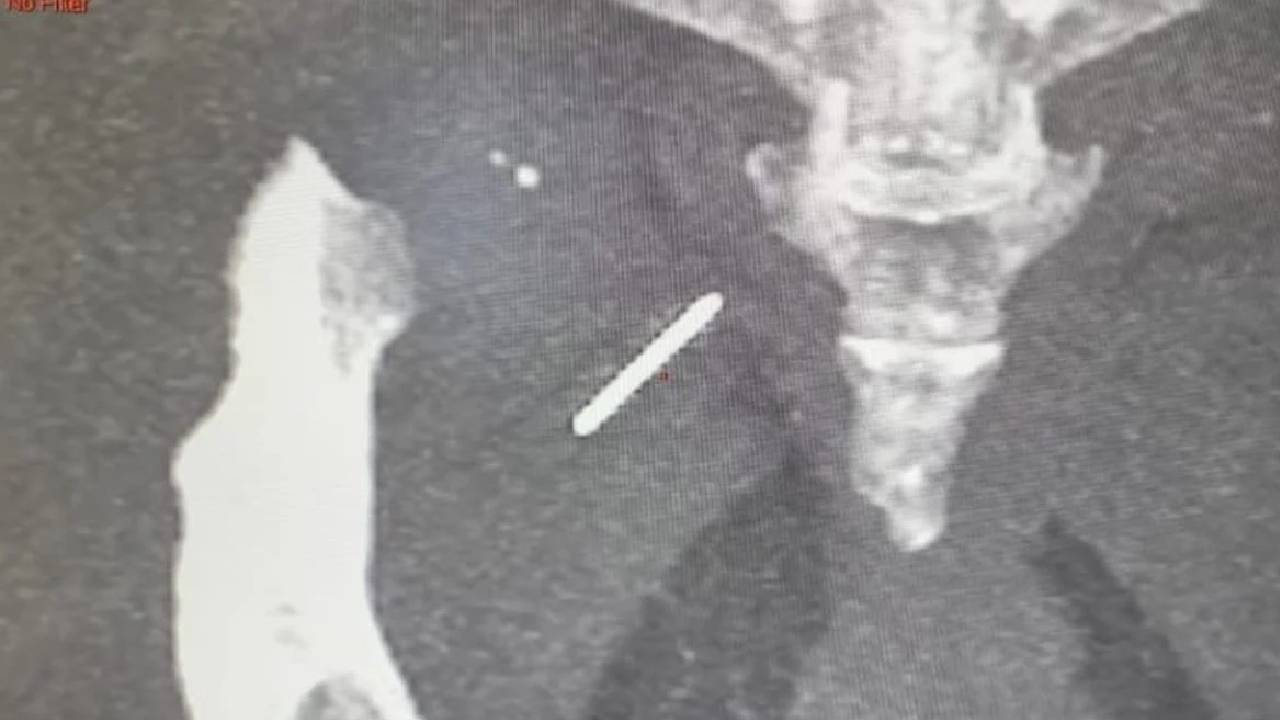

Needle Stuck In Hip: అత్యంత అరుదైన కేసులో ఒక మహిళ తుంటి భాగంలో సూది 3 ఏళ్లుగా ఉంది. దీనిని తొలగించడానికి డాక్టర్లు సర్జరీ చేయాల్సి వచ్చింది. ఢిల్లీకి చెందిన 49 ఏళ్ల రంభాదేవీ అనే మహిళ తుంటి కండరాల్లో మూడేళ్లుగా సూది ఉండిపోయింది. కుట్టుపని చేస్తుండగా అనుకోకుండా సూది ఆమె కండరాల్లోకి చొచ్చుకెళ్లింది. కుట్టుపని చేస్తుండగా, సూది మంచంపై పెట్టి ఉంచింది. ఆమె వేరే పనికి వెళ్లి వచ్చి, సూది అక్కడ ఉంచిన విషయాన్ని మరిచిపోయి దానిపై కూర్చుంది. ఆ సమయంలో ఆమెకు తీవ్రంగా నొప్పి వచ్చింది, చూసే సరికి మంచంపై సగం విరిగిన సూది కనిపించింది, మిగిలిన సగం అక్కడే ఎక్కడో పడి ఉంటుందని భావించింది.

అయితే, ఈ ఘటన జరిగినప్పటి నుంచి ఆమె తుండి భాగం అసౌకర్యంగా అనిపించడం ప్రారంభమైంది. కాలక్రమేణా దాని తీవ్రత పెరుగుతూ వచ్చింది. నొప్పి భరించలేక వైద్యుడిని సంప్రదించాలని నిర్ణయించుకుంది. ఎక్స్-రే తీయగా తుంటి భాగంలో సూది ఉన్నట్లు డాక్టర్లు గుర్తించారు. ఈ సూదిని వెలికితీసే సర్జరీ కోసం ప్రత్యేకంగా సీ-ఆర్మ్ అనే పరికరాన్ని ఉపయోగించారు. అయితే, సర్జరీ సమయంలో సూదిని గుర్తించడం చాలా కష్టంగా మారింది. దీంతో చాలా ఎక్స్-రే ఇమేజెస్ ఆధారంగా సూది ఉన్న భాగాన్ని ఖచ్చితంగా కనుగొని, దానిని వెలికితీశారు. ఇది చాలా సంక్లిష్టమైందిగా ఆస్పత్రి జనరల్ సర్జరీ విభాగంలో సీనియర్ డాక్టర్ తరుణ్ మిట్టల్ చెప్పారు.